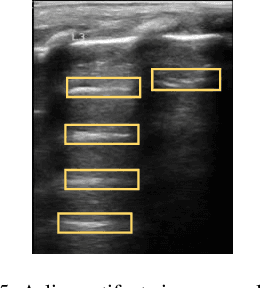

Abstract:Over the last few decades, Lung Ultrasound (LUS) has been increasingly used to diagnose and monitor different lung diseases in neonates. It is a non invasive tool that allows a fast bedside examination while minimally handling the neonate. Acquiring a LUS scan is easy, but understanding the artifacts concerned with each respiratory disease is challenging. Mixed artifact patterns found in different respiratory diseases may limit LUS readability by the operator. While machine learning (ML), especially deep learning can assist in automated analysis, simply feeding the ultrasound images to an ML model for diagnosis is not enough to earn the trust of medical professionals. The algorithm should output LUS features that are familiar to the operator instead. Therefore, in this paper we present a unique approach for extracting seven meaningful LUS features that can be easily associated with a specific pathological lung condition: Normal pleura, irregular pleura, thick pleura, Alines, Coalescent B-lines, Separate B-lines and Consolidations. These artifacts can lead to early prediction of infants developing later respiratory distress symptoms. A single multi-class region proposal-based object detection model faster-RCNN (fRCNN) was trained on lower posterior lung ultrasound videos to detect these LUS features which are further linked to four common neonatal diseases. Our results show that fRCNN surpasses single stage models such as RetinaNet and can successfully detect the aforementioned LUS features with a mean average precision of 86.4%. Instead of a fully automatic diagnosis from images without any interpretability, detection of such LUS features leave the ultimate control of diagnosis to the clinician, which can result in a more trustworthy intelligent system.